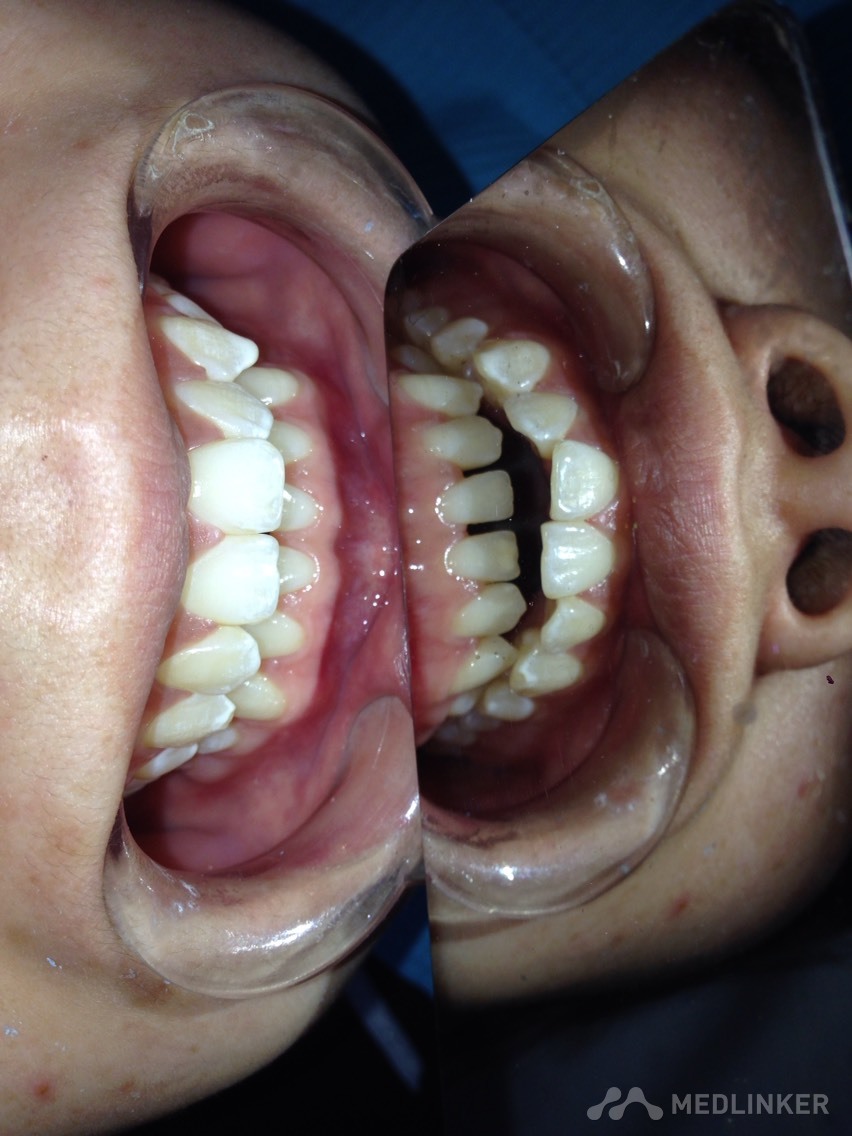

患者女,23岁,想做隐形无托槽矫正

上颌前牙牙列拥挤,下颌前牙散在间隙,下颌双侧第一磨牙缺失多年,开合